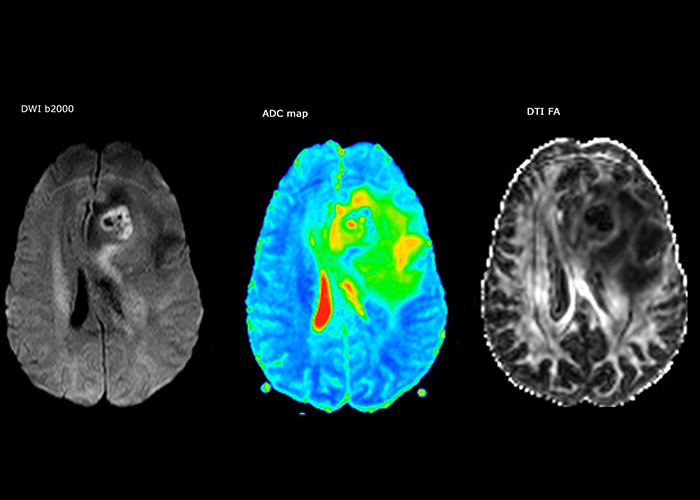

“The biggest challenges are properly characterizing the lesion and giving the surgeon all the information needed, such as the location of vessels and functional areas. Sometimes a very comprehensive exam is necessary, such as when a mass has been discovered at another hospital after which the patient is referred to us. We then do both lesion characterization and preoperative imaging in one exam, so both morphologic and functional assessment. For morphologic assessment we will use pre- and post-contrast T1-weighted imaging, FLAIR to assess infiltration, and diffusion. For functional characterization we will perform perfusion, spectroscopy, and susceptibility weighted imaging to look for micro vessels or micro hemorrhage inside the lesion[4]. For preoperative imaging we perform specific morphologic imaging that is compatible with the navigation system; depending on the location of the tumor, we would do fMRI or DTI.”

Every minute counts in stroke imaging

“In France, stroke is usually imaged with MRI, not CT, even for emergency treatment. This is because MRI helps us directly visualize ischemia in the acute phase, but can also help rule out differentials such as MS and hematoma. In addition, we can assess the intracranial and extracranial vessels during the same examination,” says Dr. Savatovsky.

The first challenge in MRI of stroke is speed. The patient typically arrives from an ambulance in the MRI preparation room and the installation is done on a separate dock outside the scanner room. “The venous access is placed during the neurological examination. If the delay from the first symptoms allows the patient to receive thrombolysis we do a very fast examination that typically lasts about 11 minutes including the pre-scans. In the case of transient ischemic stroke we usually add ASL perfusion because in some symptoms with negative diffusion, ASL sometimes indicates a vascular origin.”

“Ingenia provides great flexibility in the parameters setting. We can tune a sequence the way we want,” says Dr. Savatovsky. “For example, in a stroke exam we use a FLAIR sequence of about two minutes instead of the four-minute FLAIR we use for MS. The diffusion is 30 seconds, the T2*-weighted scan is 30 seconds, the angiography scan time is less than one minute. Ingenia is a great scanner in that situation; even with these fast sequences we can achieve good images with good SNR. When the first sequence tells us that it’s not an ischemic stroke but a hemorrhagic stroke, we may switch to a time-resolved angiography to look for vascular malformations and venous thrombosis.

“Every center is different, but for me the ideal protocol for stroke includes diffusion weighted imaging, FLAIR, and fast susceptibility imaging,” says Dr. Savatovsky. “Our fast susceptibility weighted imaging takes 50 seconds, so it’s as fast as T2*-weighted imaging. It visualizes hemorrhage but also the clots. We also do 3D MR angiography that provides information on cervical and brain vessels. If the patient does not need immediate treatment, or if additional information is needed to decide on treatment, we might also add perfusion imaging and post-contrast T1-weighted imaging.”